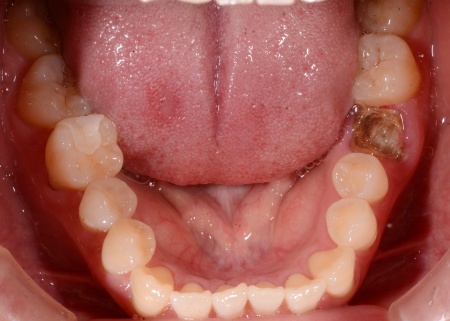

治療前

| 診断結果 | 拝見したところ、左下奥歯(第1大臼歯)の被せ物が外れていました。 被せ物の土台となっていた歯の根を確認すると割れており、これが原因で歯ぐきの腫れや痛みが引き起こされたと考えられます。 根が割れた歯は治療して残すことが難しく、またこのまま放置すると炎症が広がりまわりの歯にも影響を及ぼす可能性があるため、抜歯が必要です。 以上のことから、抜歯後に抜歯部位を補う治療が必要と診断しました。 |